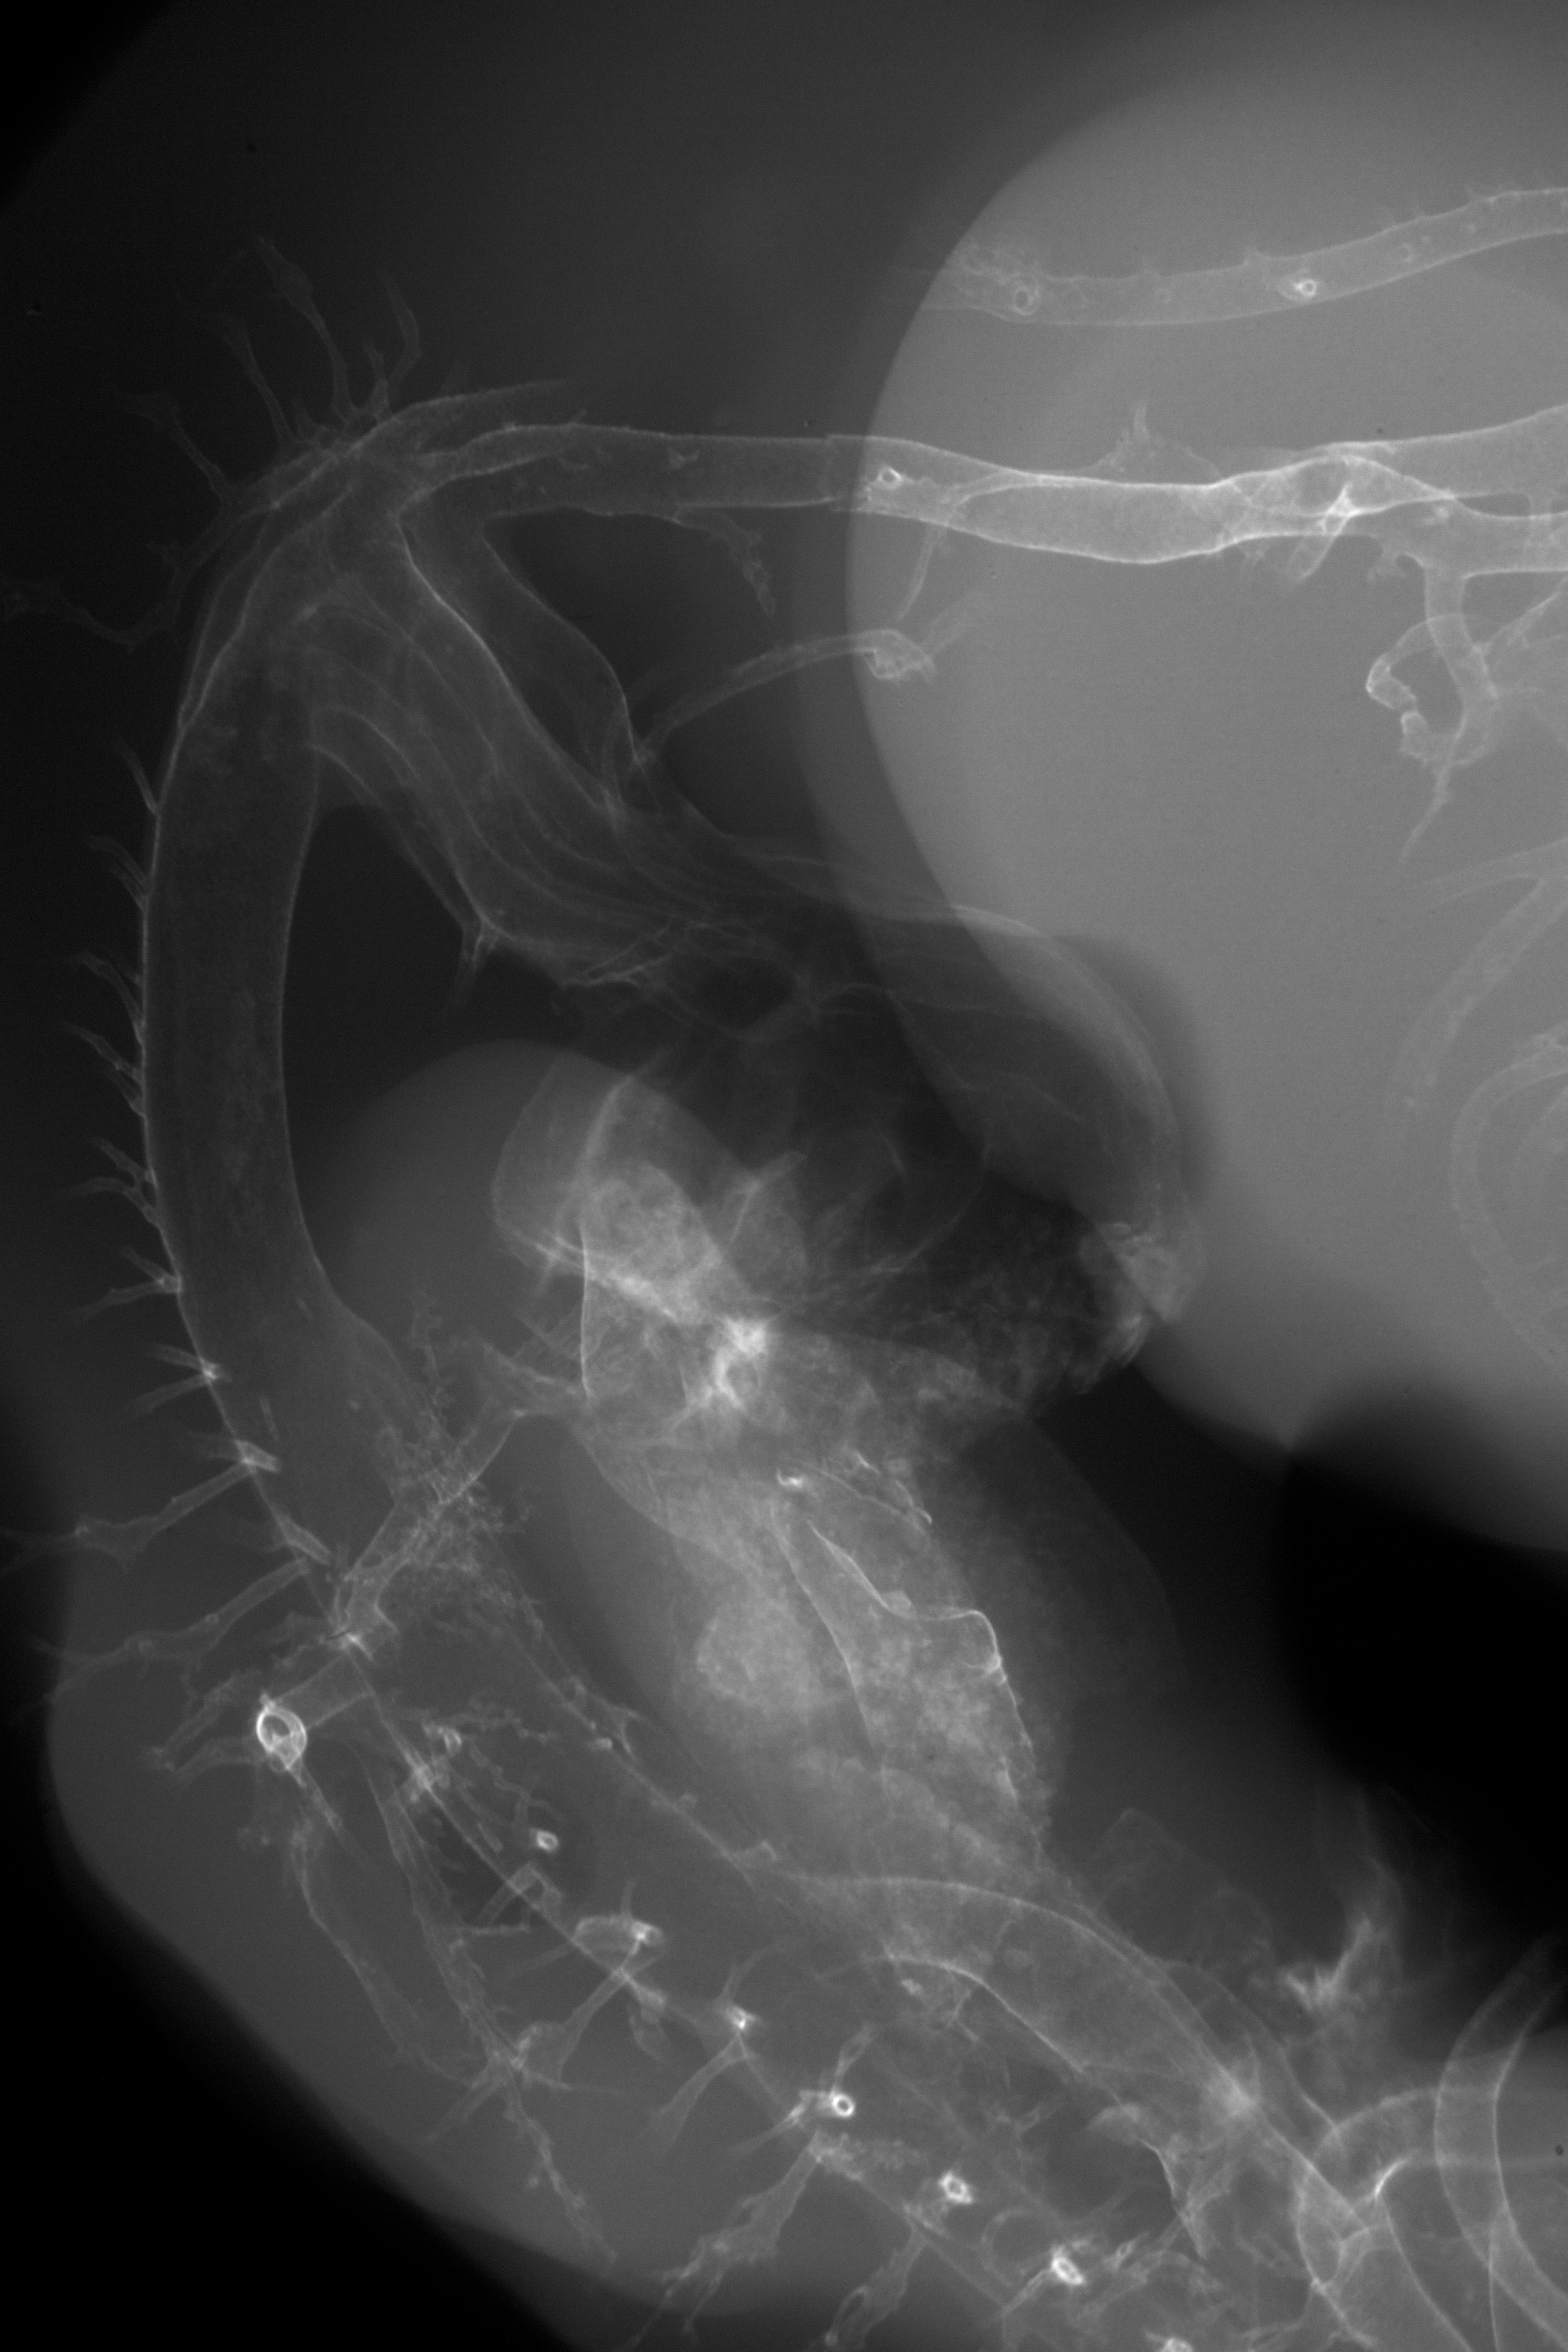

Chick Embryo Microangiography

Hamburger-Hamilton (HH) Stage 27 (approx. 5 - 5.5 days)

X-Ray Micrographs